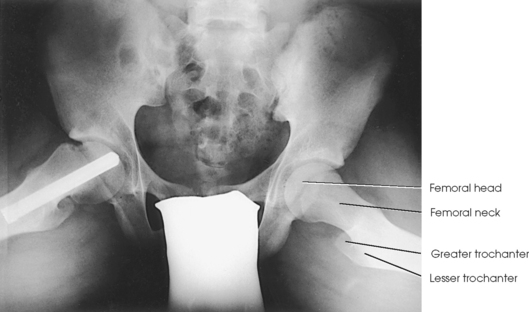

The femur is the longest, strongest, and heaviest bone in the body. The proximal end of the femur consists of a head, a neck, and two large processes: the greater and lesser trochanters (Fig. 7-4). The smooth, rounded head is connected to the femoral body by a pyramid-shaped neck and is received into the acetabular cavity of the hip bone. A small depression at the center of the head, the fovea capitis, attaches to the ligamentum capitis femoris (Fig. 7-5; see Fig. 7-4). The neck is constricted near the head but expands to a broad base at the body of the bone. The neck projects medially, superiorly, and anteriorly from the body. The trochanters are situated at the junction of the body and the base of the neck. The greater trochanter is at the superolateral part of the femoral body, and the lesser trochanter is at the posteromedial part. The prominent ridge extending between the trochanters at the base of the neck on the posterior surface of the body is called the intertrochanteric crest. The less prominent ridge connecting the trochanters anteriorly is called the intertrochanteric line. The femoral neck and the intertrochanteric crest are two common sites of fractures in elderly adults. The superior portion of the greater trochanter projects above the neck and curves slightly posteriorly and medially.

Fig. 7-4 Proximal right femur. A, Anterior aspect. B, Medial aspect. The body is positioned 15 to 20 degrees posterior from head. C, Posterior aspect. D, Posterior aspect of right proximal human femur. Note anatomic details and compare with C.